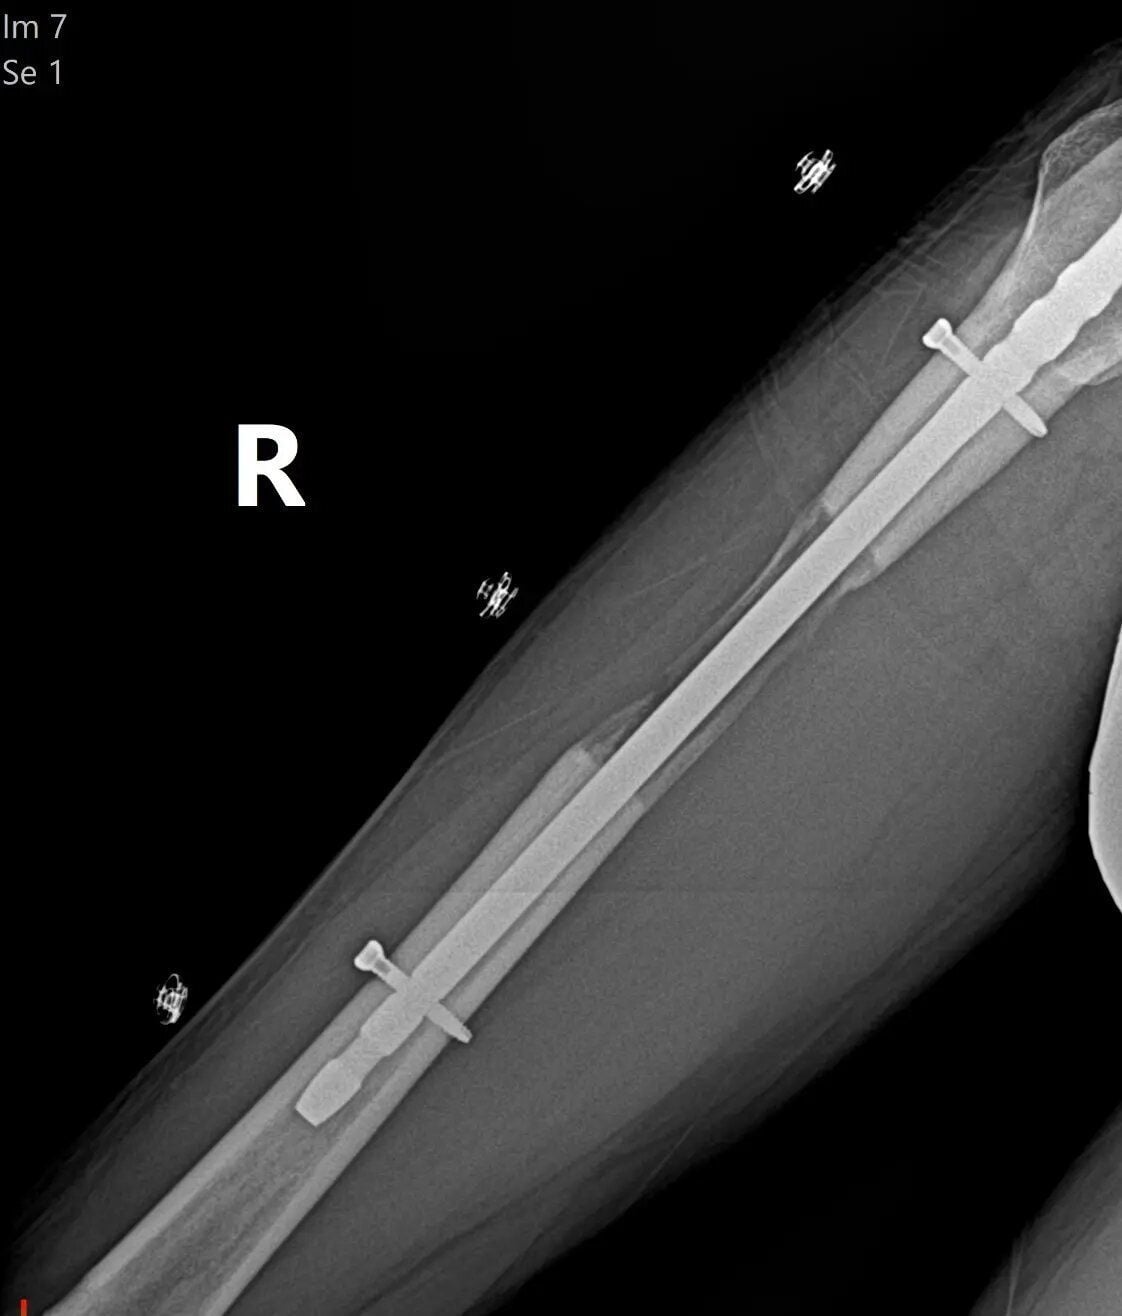

Наприкінці минулого року йому зробили в Туреччині першу із шести операцій, у ході яких кістку розрізали навпіл, вставляли стрижень та прикріплювали зовнішні фіксатори, які під час повороту подовжували кістку протягом 90 днів.

"Після закінчення 90 днів, коли ви досягнете бажаного зросту, що становить максимум 10 см на стегні і 7 см на гомілці, зовнішній фіксатор видаляється, а внутрішній стрижень залишається на місці. Коли нова кістка нарешті приросла, стрижень видаляють, але це може зайняти до року", - пояснив він.